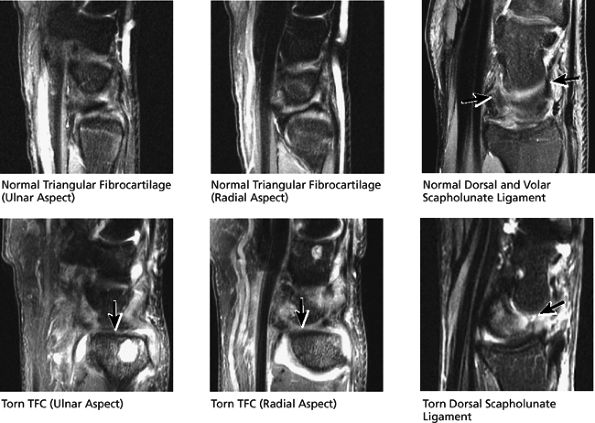

similar to the meniscus. Tears of the TFC are visualized as defects or gaps in the substance of the TFC. Tears of the membranous portion of the TFC manifest as a gap with a diastasis between the two ends of the bow-tie. The scapholunate and lunotriquetral ligaments are harder to visualize on sagittal images. However, tears of the dorsal or volar components of these ligaments, or ganglion cysts extending through these ligaments, are occasionally seen and further characterized on sagittal images.

The intrinsic carpal ligaments, including the scapholunate and lunotriquetral ligaments

The triangular fibrocartilage, including the dorsal and volar margins